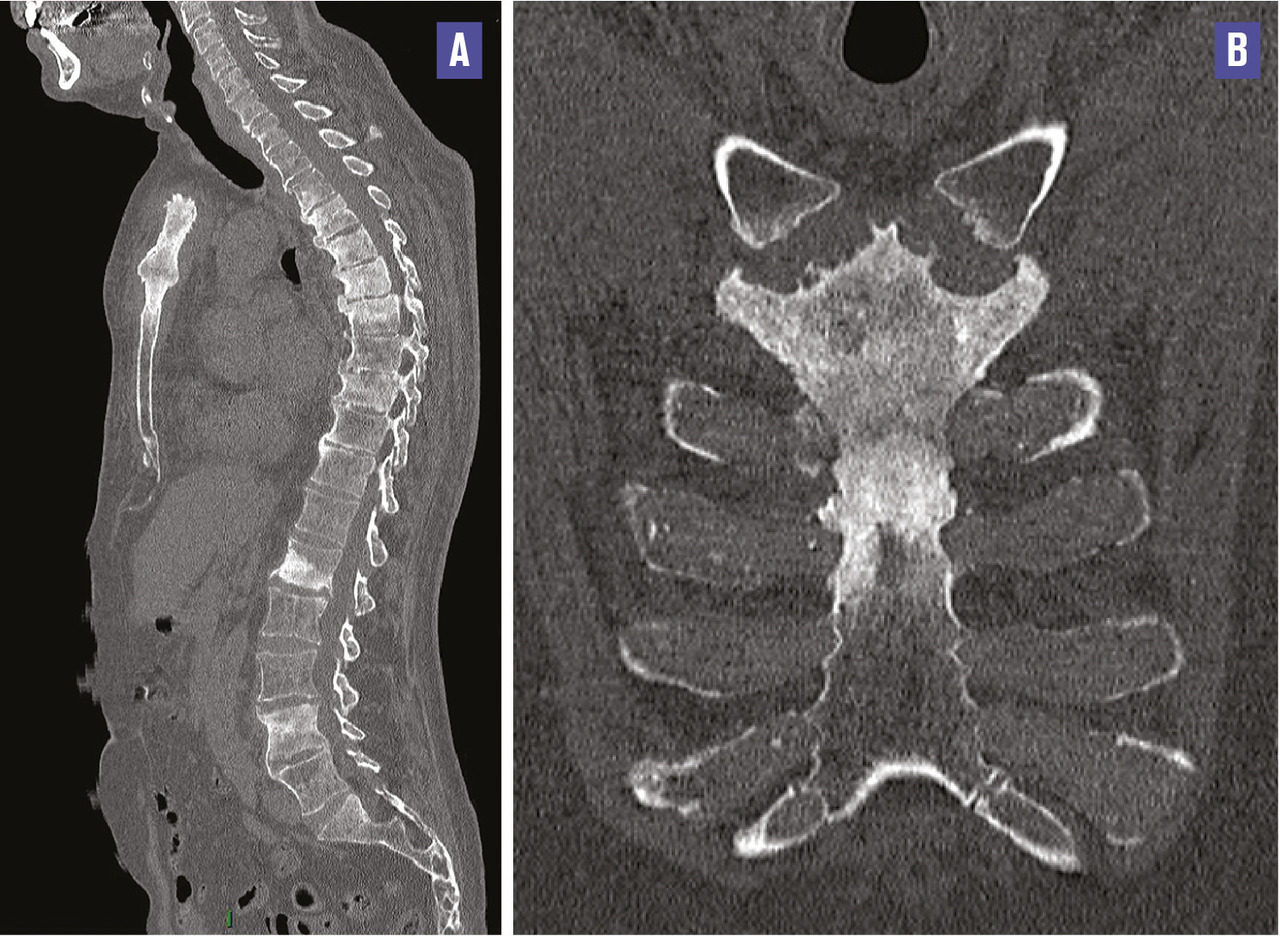

Cet homme de 64 ans, sans antécédent notable, consultait pour des douleurs rachidiennes et chondrocostales de rythme inflammatoire évoluant depuis 2012, sans manifestations digestives, ophtalmologiques ou cutanées. Il n’avait ni douleurs abdominales, ni fièvre, ni amaigrissement récent. L’examen clinique notait un syndrome rachidien, l’absence de souffle cardiaque ou d’anomalies cutanées. La tomodensitométrie thoraco-abdominopelvienne (v. figure ) montrait des lésions ostéocondensantes au niveau du rachis et du sternum avec des ossifications ligamentaires antérieures et des érosions des plateaux vertébraux, ainsi qu’une ankylose manubrio-sternale, évoquant un syndrome SAPHO. Un traitement par bisphosphonates était prescrit (et le patient perdu de vue).